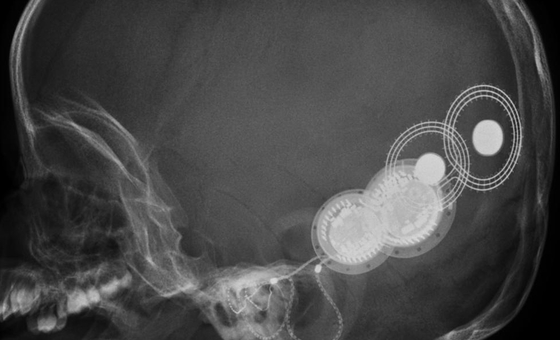

Aplicación está dirigida específicamente para Otorrinolaringólogos y otros profesionales del sector, residentes y especialistas. Con ella, podrá obtener toda la información sobre las enfermedades otorinolaringológicas de cada especialidad y sus síntomas.